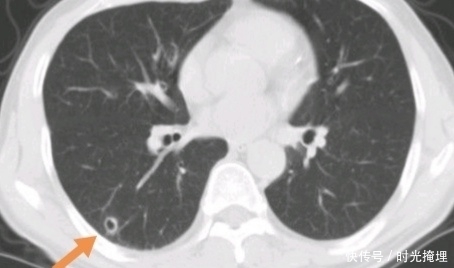

这位64岁的老人,胸闷咳嗽,CT发现右下肺小空洞样病灶:

文章插图

仅仅过了五个月,就明显增大了已经侵犯了胸膜: